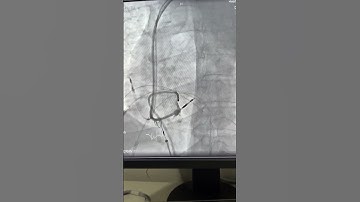

Conduction System Pacing CSP (Left bundle branch pacing)